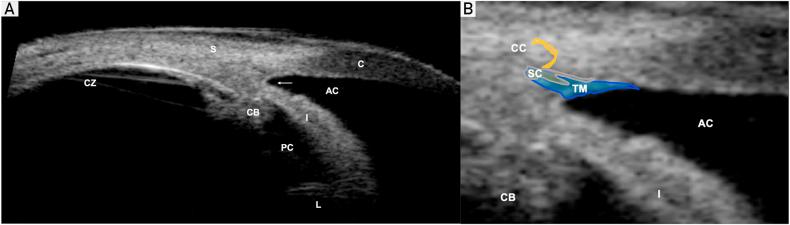

Glaucoma is the leading cause of blindness throughout the world (after cataracts); therefore, general physicians should be familiar with the diagnosis and management of affected patients. Glaucomas are usually categorized by the anatomy of the anterior chamber angle (open vs narrow/closed), rapidity of onset (acute vs chronic), and major etiology (primary vs secondary). Most glaucomas are primary (ie, without a contributing comorbidity); however, several coexisting ophthalmic conditions may serve as the underlying etiologies of secondary glaucomas. Chronic glaucoma occurs most commonly; thus, regular eye examinations should be performed in at-risk patients to prevent the insidious loss of vision that can develop before diagnosis. Glaucoma damages the optic nerve and retinal nerve fiber layer, leading to peripheral and central visual field defects. Elevated intraocular pressure (IOP), a crucial determinant of disease progression, remains the only modifiable risk factor; thus, all current treatments (medications, lasers, and operations) aim to reduce the IOP. Pharmacotherapy is the usual first-line therapy, but noncompliance, undesirable adverse effects, and cost limit effectiveness. Laser and surgical treatments may lower IOP significantly over long periods and may be more cost effective than pharmacotherapy, but they are plagued by greater procedural risks and frequent treatment failures. Traditional incisional procedures have recently been replaced by several novel, minimally invasive glaucoma surgeries with improved safety profiles and only minimal decreases in efficacy. Minimally invasive glaucoma surgeries have dramatically transformed the surgical management of glaucoma; nevertheless, large, randomized trials are required to assess their long-term efficacy.